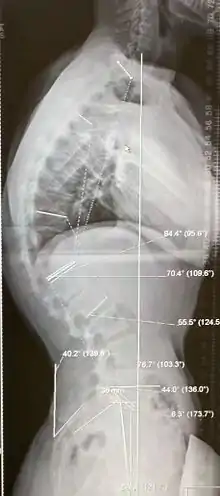

| Scheuermann's disease on lateral Xray of the T spine | |

Diagnosis is typically by medical imaging. The degree of kyphosis can be measured by Cobb's angle and sagittal balance.